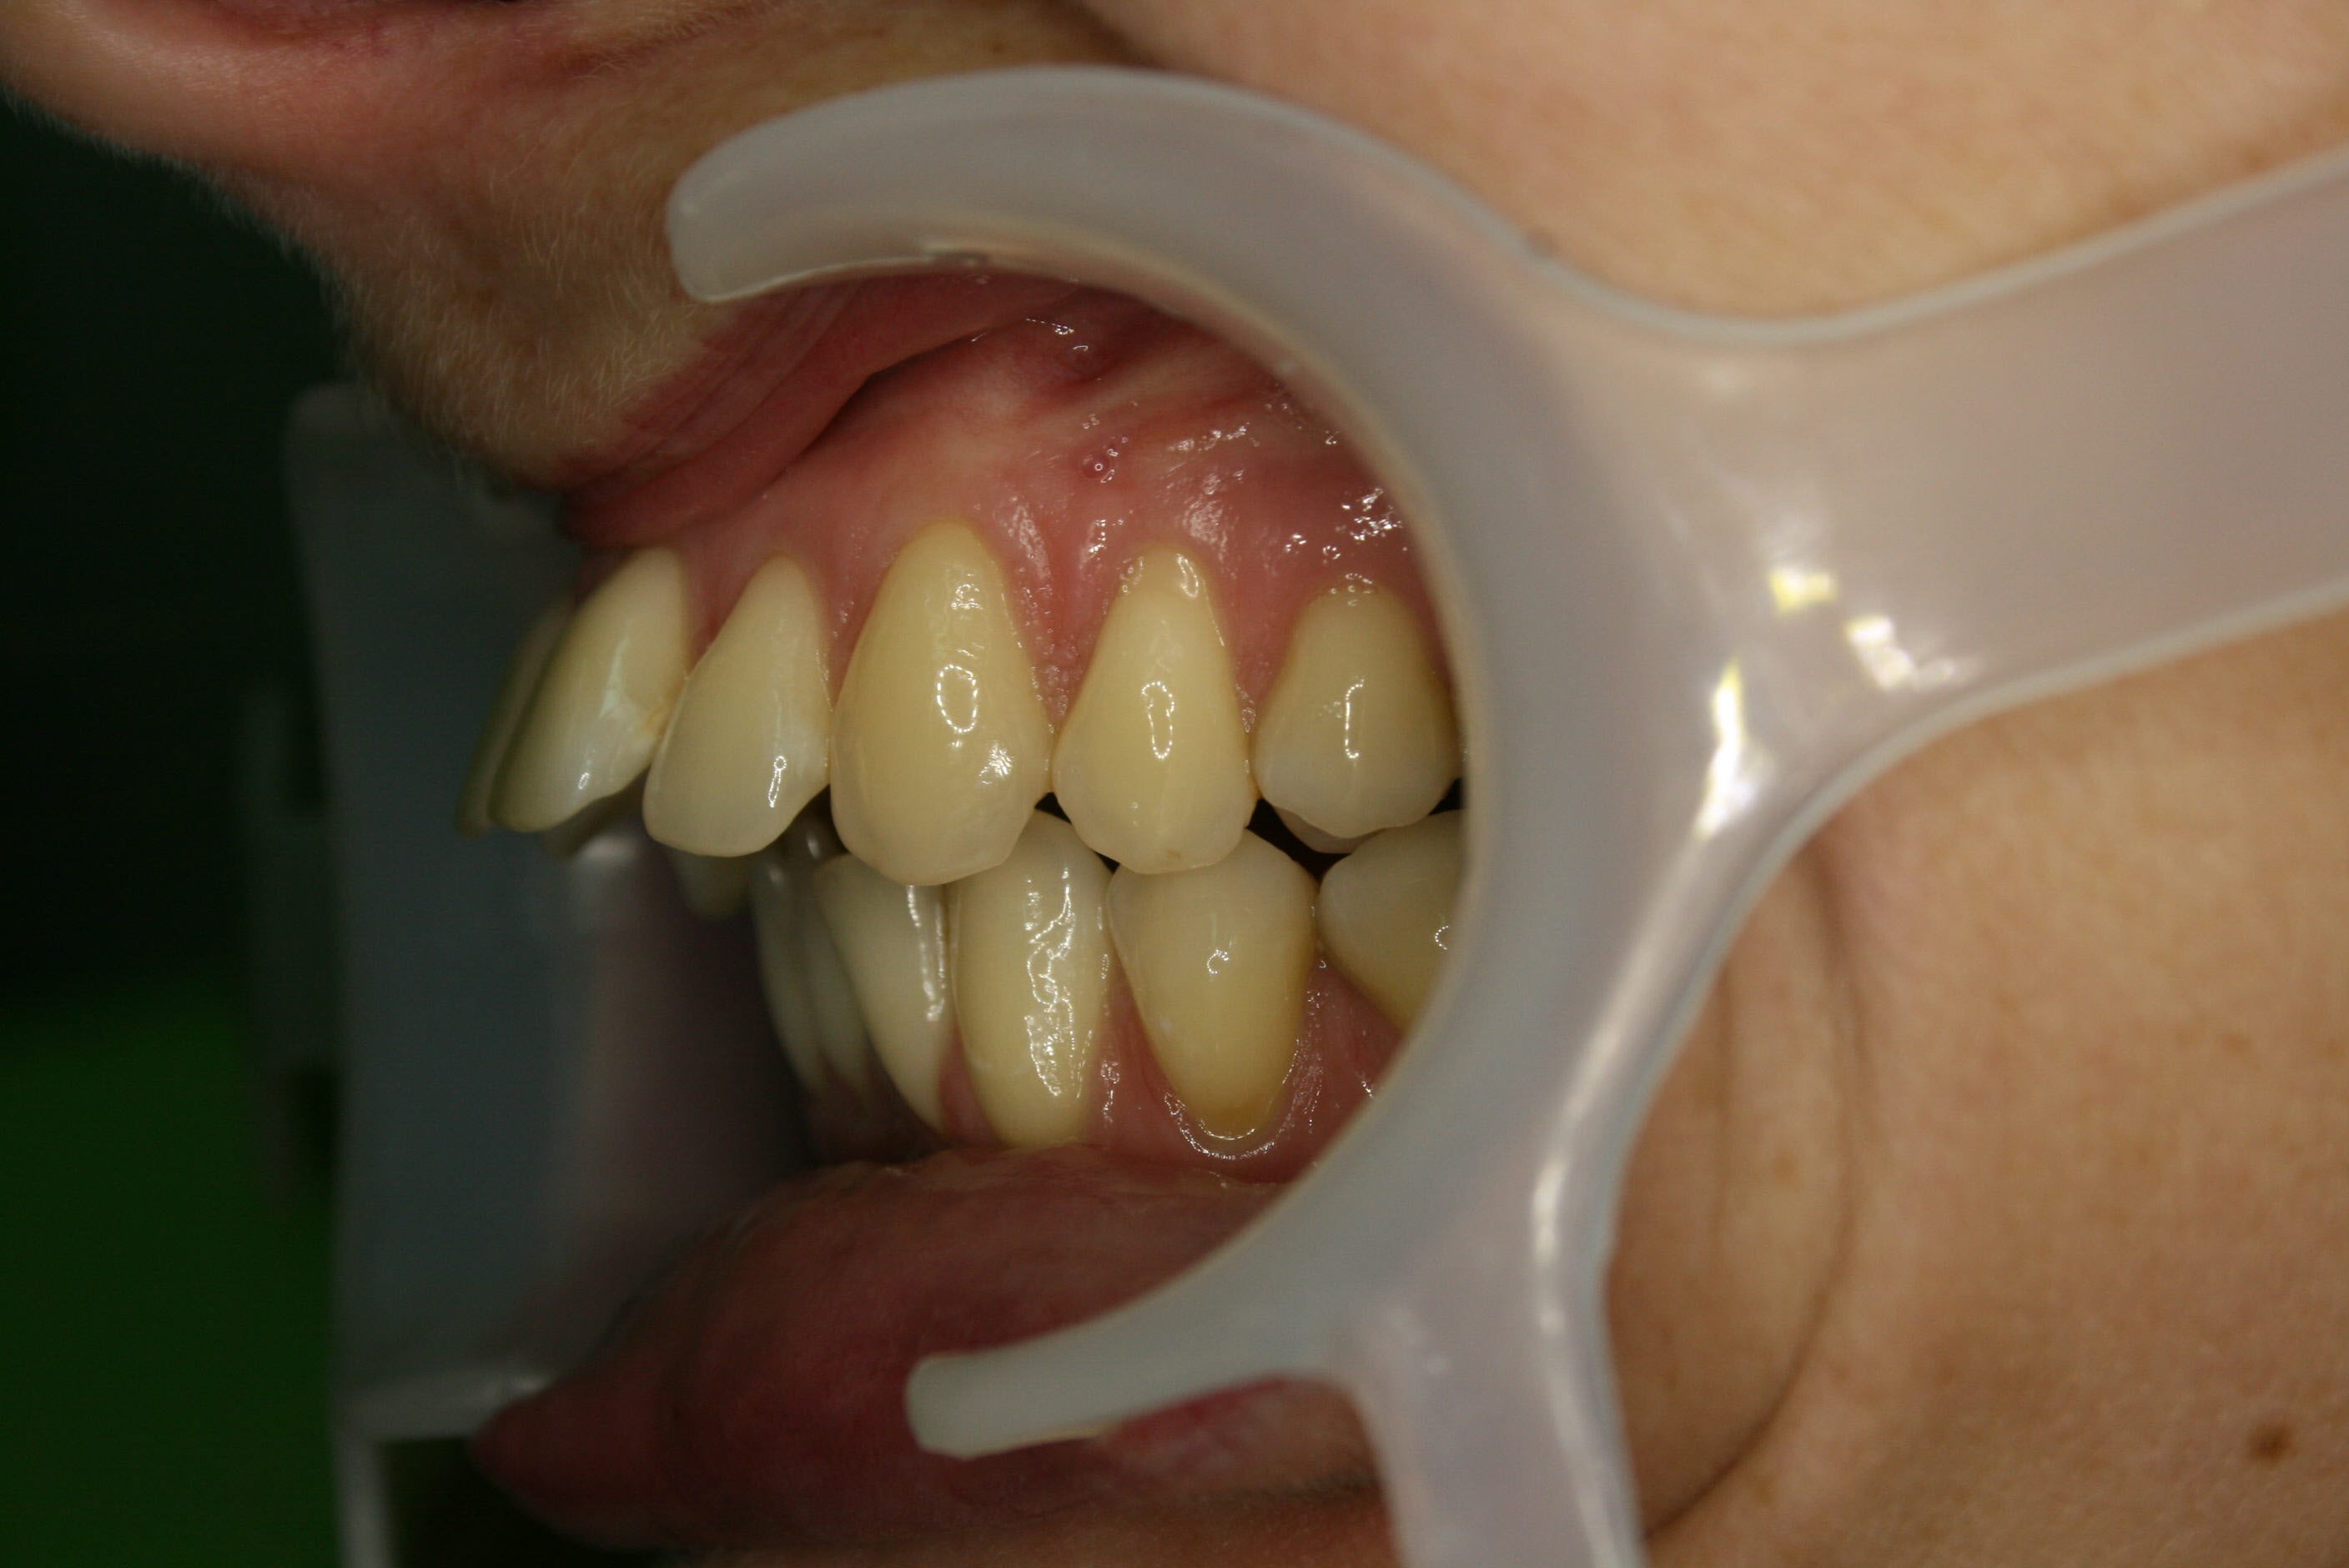

Lückenschluß in der Seitenansicht; hier ist gut zu erkennen, daß es gelungen war, den Lückenschluß von vorne her und achsengerecht auszuführen.

Nach der Behandlung